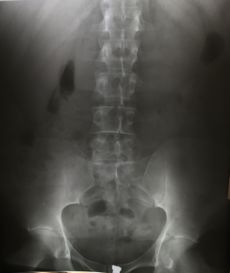

التصوير الشعاعي إنگليزية: Radiography: وهو يستخدم الأشعة السينية لرؤية الأجزاء غير المرئية أو صعبة التصوير. الهدف الأساسي من الأشعة السينية المستخدمة في التشخيص هو تصوير داخل الجسم، وبشكل خاص العظام والتي يمكن رؤيتها بدقة مثلى (128 تدرج للون الرمادي).

Projectional radiography

Computed tomography